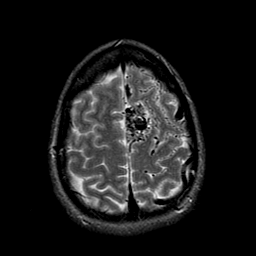

Vascular Malformation:T2-weighted MR #1 -- Slice #20

[Home][Help][Clinical] Slice 20